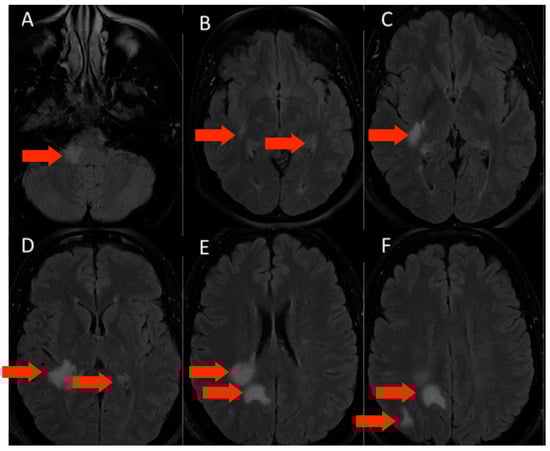

3.1.1. Patient 1

3.1.2. Patient 2

3.1.3. Patient 3